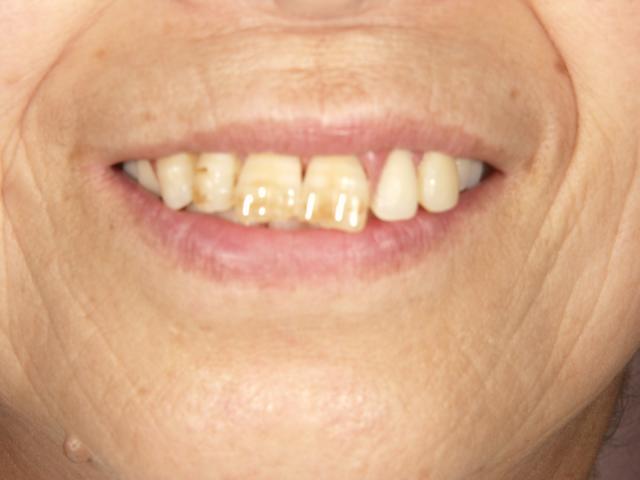

ノンクラスプデンチャー 金属の見えないようにしたい!!

2006/07/10

担当医;院長神保

50代後半女性 上の歯の見栄えを自然にしたい希望。

前歯3本 奥歯3本のみしか残ってませんでした。

上の歯の見栄えを自然に

前歯3本はセラミックス使用 義歯はノンクラスプデンチャー設計です。

入れ歯を入れているのが判らなくなりました!!

上の歯の見栄えを自然に 上の歯の見栄えを自然に

また入れ歯を外しても前歯が自然なので外食も怖くなくなったそうです。

よかったですね!!